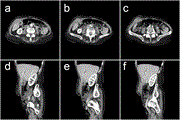

Fluorescence guidance during robotic resection of bladder wall endometriosis: case report and technique

Yasnaia Bruneel and others

Journal of Surgical Case Reports, Volume 2023, Issue 10, October 2023, rjad604, https://doi.org/10.1093/jscr/rjad604